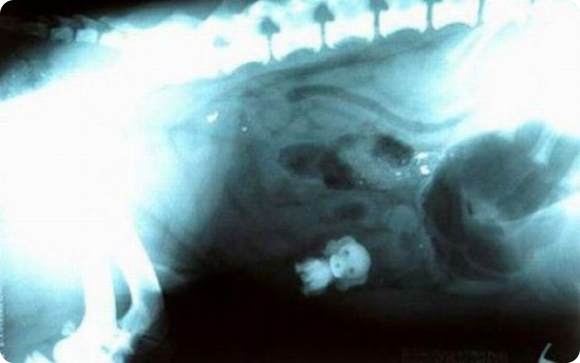

Детали конструктора LEGO изготавливают из пластмассы, в состав которой входит специальное вещество сульфат бария. Эта соль не токсична для организма, так как не растворяется в воде. Главное ее свойство состоит в том, что ее хорошо видно рентгеновских снимках. Это значит, что если ребенок случайно проглотит деталь, то ее можно будет легко обнаружить.